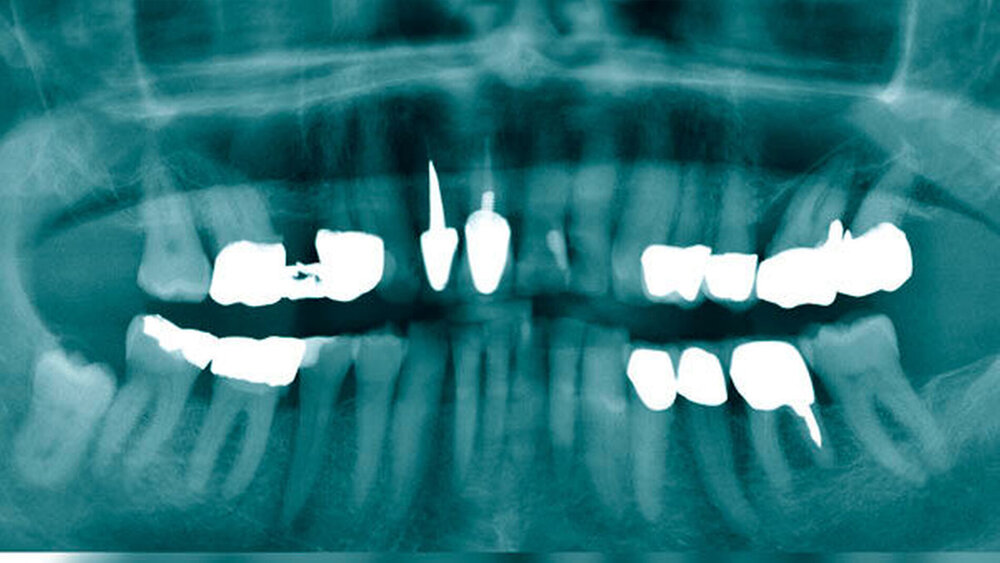

Ein 83-jähriger Mann stellte sich nach Überweisung der niedergelassenen Kollegen mit Bitte auf Therapieübernahme mit einer Schwellung der Glandula parotis links vor. Bei der zuvor durchgeführten zahnärztlichen Diagnostik waren in der Panoramaschichtaufnahme (Abbildung 1) keine Auffälligkeiten der knöcherneren Strukturen zu erkennen. Das extern veranlasste CT zeigte eine Raumforderung der Glandula parotis links.

Bei der klinischen Untersuchung zeigte sich eine Schwellung der Regio parotideo-masseterica links. An der Glandula parotis war linksseitig kaudal eine Raumforderung palpabel, die prall-elastisch und verschieblich anmutete. Hinweise auf eine Infektion in Form der klassischen Entzündungszeichen lagen nicht vor. Aus beiden Stenon-Gängen ließ sich klares Speichelsekret exprimieren. Die Sensibilität und die Motorik im Gesichtsbereich zeigten keinen pathologischen Befund. Der enorale Befund der Mundschleimhaut erwies sich als unauffällig bei suffizientem Zahnersatz. Konservierend zeigten sich Zahn 26 und 27 jedoch als nicht erhaltungswürdig.